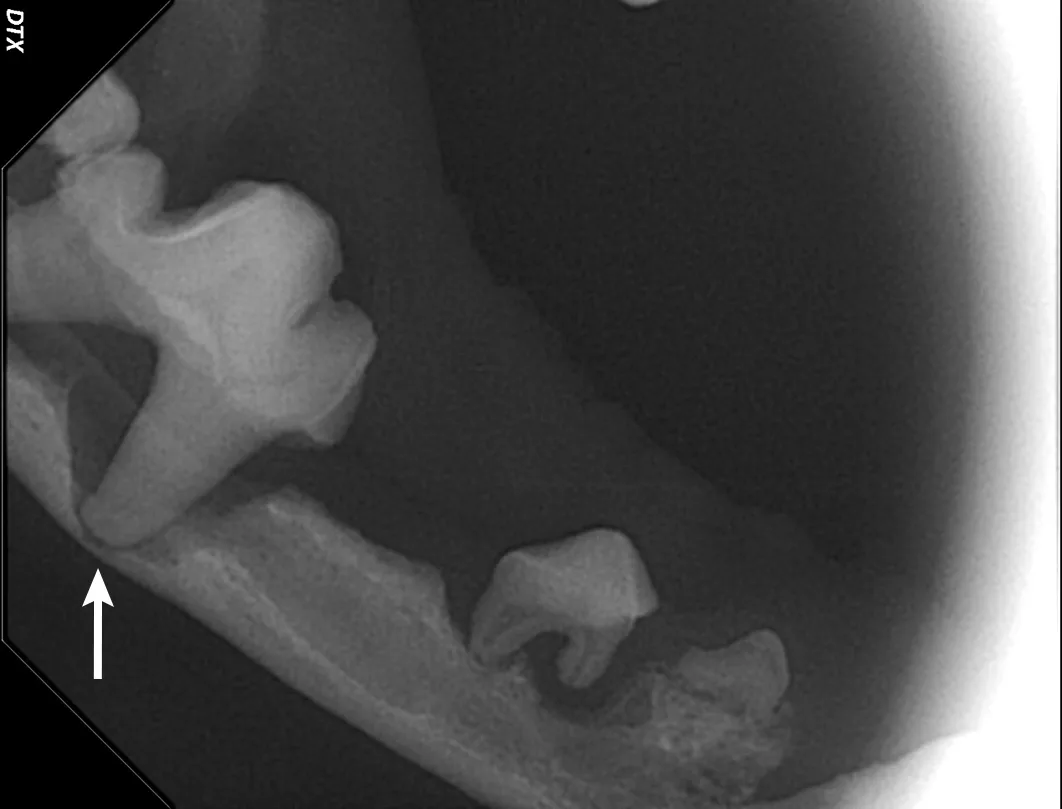

Iatrogenic fracture of the jaw can be a serious complication of surgical extractions and is most commonly associated with surgical extraction of mandibular canine teeth in dogs and cats and mandibular first molar teeth in dogs (Figure 10). These extractions can be difficult to perform, as the root apexes are often located in close proximity to the ventral cortex of the mandible, possibly leading to significant bone loss when severe disease is present and increasing the risk for iatrogenic fracture (Figure 11).

Pathologic fracture (arrow) secondary to severe periodontal disease of the right mandibular first molar tooth in a dog

Severe periodontal disease affecting the right mandibular first molar tooth in a dog. Careful extraction technique is necessary to extract the tooth without creating an iatrogenic fracture.

Preoperative intraoral radiographs are critical for assessing fracture risk, especially prior to surgical tooth extraction, and can be used to modify the procedure or refer a patient with high fracture risk to a board-certified veterinary dentist.